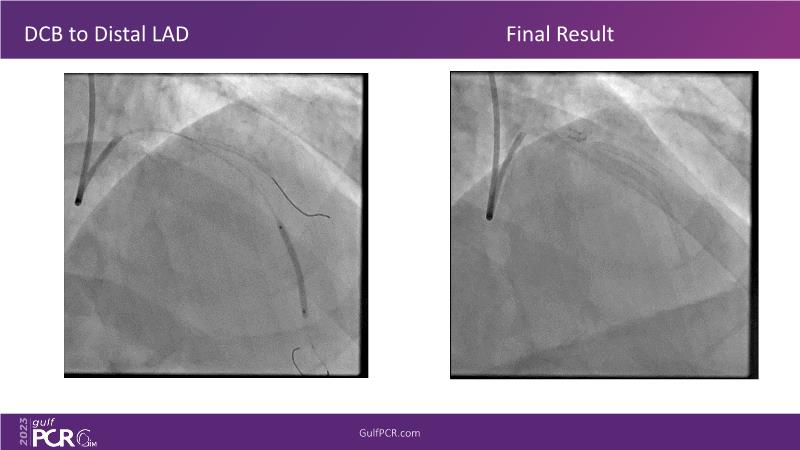

This session is a valuable resource for grasping innovative strategies in handling bifurcation and extended diffuse lesions through dedicated stenting solutions. Explore insights into the advanced Myval next-generation THV technology, unveiling its distinctive features, procedural advantages, and clinical outcomes across a diverse patient pool. Gain understanding into the CorAlign technique, ensuring accurate commissural and coronary alignment while maintaining coronary access. Additionally, delve into the techniques for precise sizing, positioning, and deploying of Myval THV.

- To understand novel tools and techniques for effective management of bifurcation lesions and long diffused lesions using dedicated stenting solutions